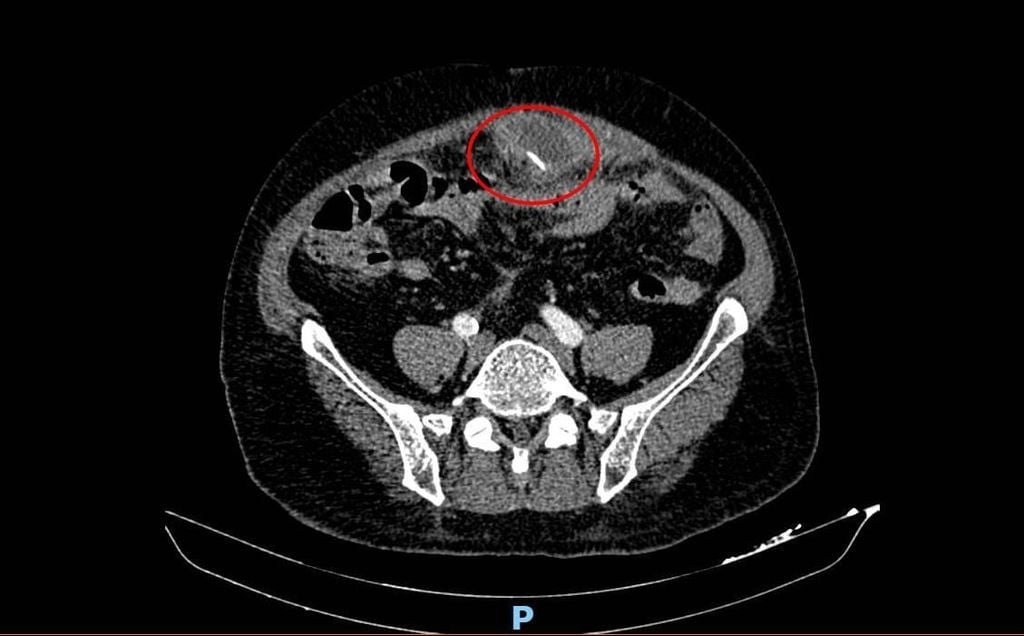

Tại bệnh viện, kết quả CT scan ổ bụng ghi nhận hình ảnh ổ áp xe vùng bụng ngang – dưới rốn. Điều đặc biệt, bác sĩ còn phát hiện một cấu trúc đậm độ cao dạng dị vật sắc nhọn bên trong ổ áp xe.

Trong quá trình mổ, các bác sĩ ghi nhận một ổ áp xe khoảng 8 cm chứa nhiều mủ vùng hạ vị. Bất ngờ, một dị vật là xương cá dài khoảng 4 cm được phát hiện xuyên thủng thành ruột, di chuyển ra ngoài và trở thành nguyên nhân gây ổ áp xe. Dị vật được lấy ra an toàn, ổ áp xe được phá và rửa sạch.